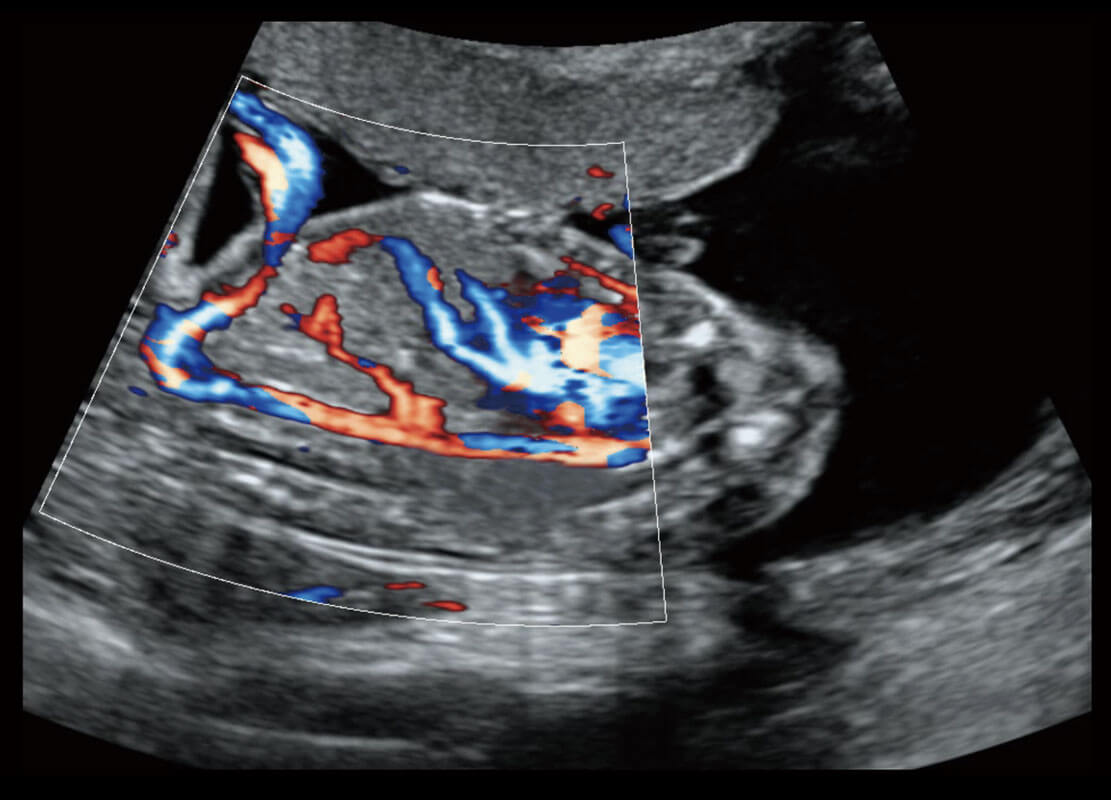

胎儿体循环

P60搭载一系列胎儿心脏成像技术,实现精细的胎儿心脏评估。

四腔切面

四腔心血流

右室双出口

胎心容积成像